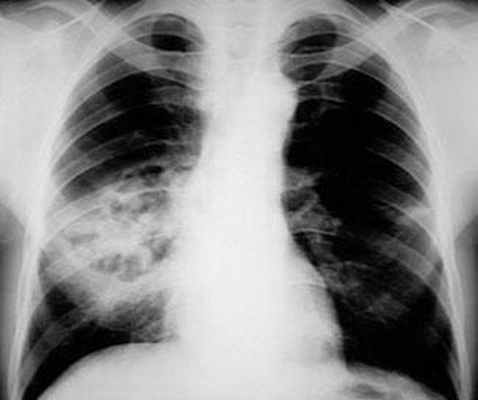

Пневмококковая пневмония, осложнившаяся некрозом и абсцессом легкого. Источник: Medscape.

Плевральный выпот может быть выявлен на обзорной рентгенограмме органов грудной клетки. Эмпиему следует подозревать у пациентов, организм которых не отвечает на соответствующую антибактериальную терапию.

Осумкованный плевральный выпот слева с распространением по косой междолевой щели. Источник: Radiopedia.

В случае возникновения диагностических трудностей необходимо провести компьютерную томографию с контрастированием. КТ-сканирование с использованием контрастного вещества может помочь дифференцировать эмпиему плевры от абсцесса легкого. Эмпиемы обычно имеют линзовидную форму и сдавливают паренхиму легкого, в то время как абсцессы легкого часто имеют нечеткую границу и не оказывают значительного влияния на окружающую легочную ткань. Также при эмпиеме плевры наблюдается диагностический признак «расщепленной плевры» — визуализация на КТ утолщенных париетальной и висцеральной плевральных листков.